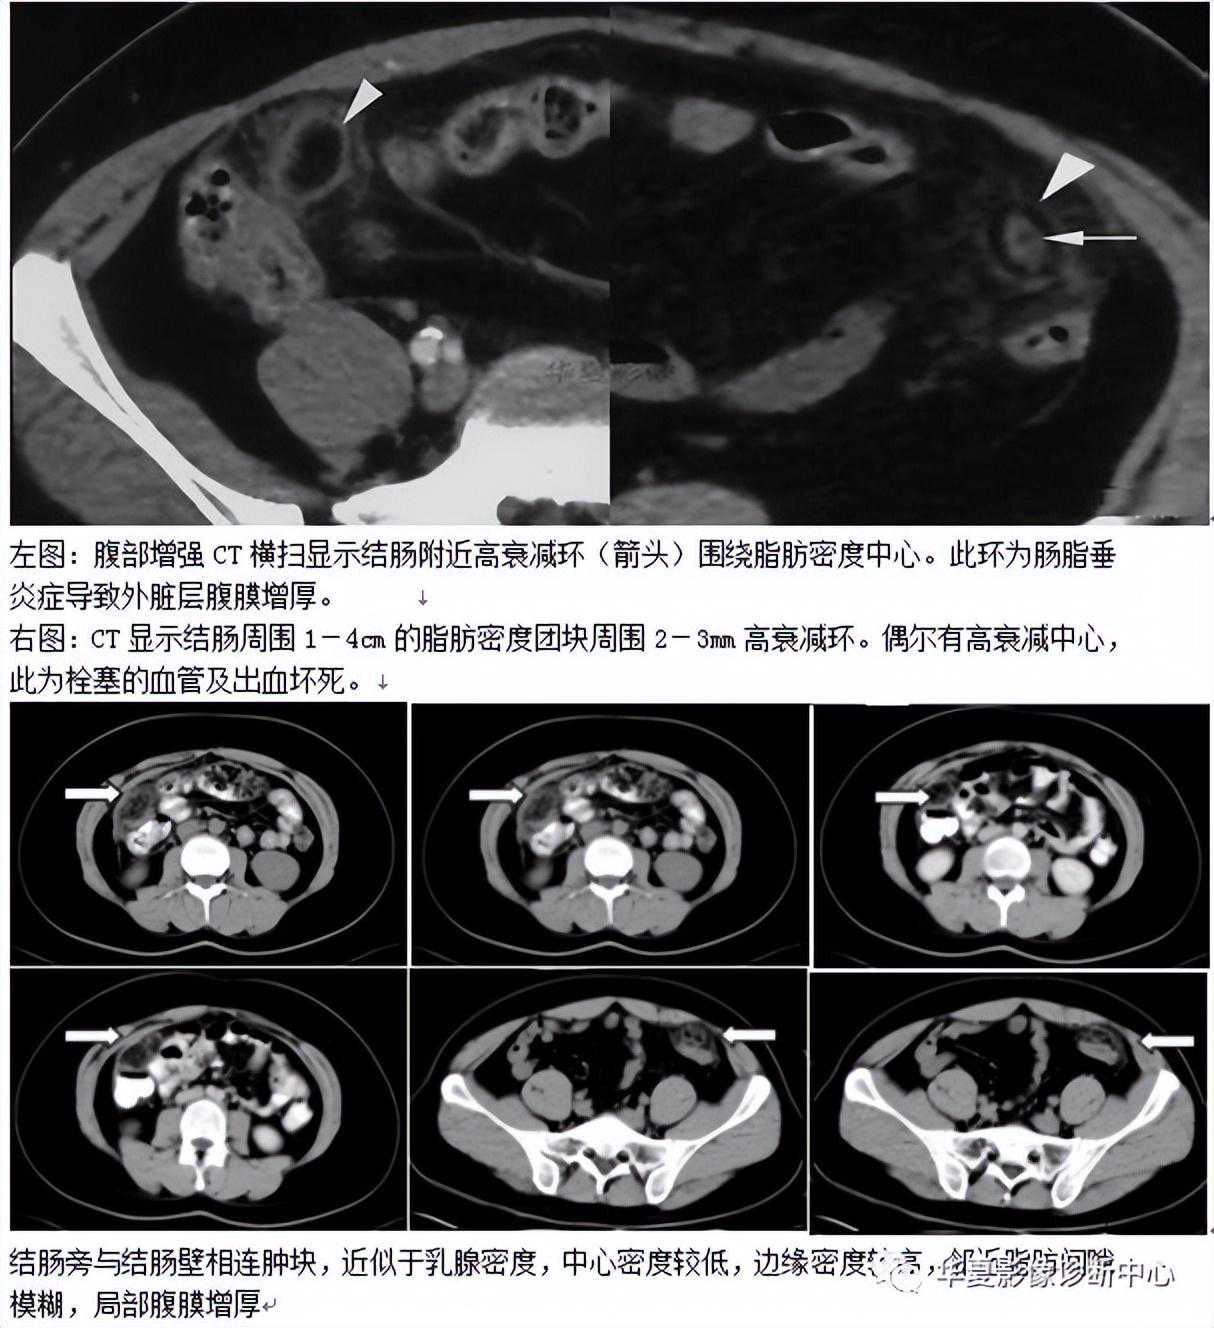

032:肝脏灌注异常(HPD)

HPD是指由各种原因引起的肝段、亚段及肝叶之间的血流灌注差异,在CT、MR动态增强扫描及肝动脉造影时表现为动脉期正常肝实质一过性楔形、三角形或类圆形强化或染色,门静脉期即恢复正常,没有占位效应、强化或染色区内可见正常血管穿行。

这种肝脏灌注异常主要表现在CT增强动脉期的一过性增强,所以又称之为一过性肝亚段强化(TSPE)。THAD作为双期CT增强扫描时一过性肝密度差异,其本质反映了肝段、亚段或肝叶之间的动脉期血流灌注差异,不能概括其他影像检查所见的本质特征,如肝动脉造影时出现的肝段染色,超声检查时出现的斜方形低回声区,MR检查时出现的肝段信号差异等,而HPD却能够反映这一不同影像表现的共同本质特征,因此,HPD更能准确反应这种现象的是实质。

影像表现

CT平扫大多数表现为等密度,少数表现为楔形或三角形低密度区,可能与门静脉分支堵塞后,富含营养的门静脉血流灌注减少,相应肝段出现营养不良性水肿,继发局部的脂肪变性有关。增强扫描时多表现为动脉期一过性楔形、三角形或类圆形异常强化区,少数为强化减低区,门静脉期恢复等密度。这种变化可累及肝段、亚段及肝叶,可多发,也可单发,多位于肝周围区域;MR表现类似于CT,平扫大多呈等T1、等T2信号,少数可表现为长T1、长T2,但MR在显示门静脉堵塞后继发改变较CT敏感。动态增强扫描时强化及分布特征类似于CT。肝动脉造影时见楔形、三角形肝段染色,可位于肝脏相关病灶周围或邻近肝段,有门静脉堵塞者间接门静脉造影可见相应区域染色缺失或减弱,有肝静脉堵塞及异位血管变异者会有相应造影表现;HPD时,超声可能表现为楔形低回声区,超声增强是否通过切面实时观察到HPD,尚无文献报道。但是本例超生检查未发现异常。